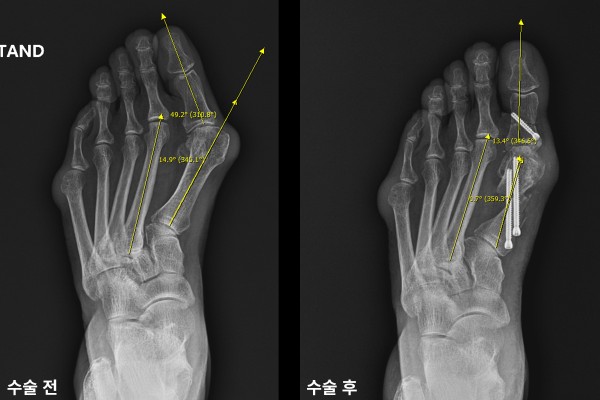

환자분의 발 상태를 정확하게 파악하기 위해 촬영한 X-RAY에서 엄지발가락이 휘어진 정도인 무지외반각은 49.2도(정상범위: 15도 이내),엄지발가락과 검지발가락 사이를 확인하는 중족골간각은 14.9도(정상범위: 9도 이내)로 좌측 발 무지외반증(Hallux valgus)을 진단하였습니다.

수술 후 무지외반각과 중족골간각 모두 정상범위내로 교정된 것이 확인됩니다.

수술 전/후 X-RAY를 비교했을 때 엄지발가락이 일자로 잘 교정된 것이 확인됩니다.